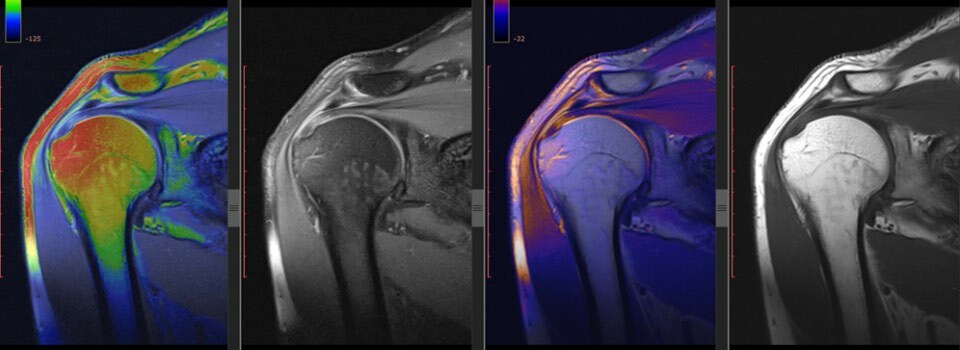

肩峰下除圧術は本当に必要なのか?

肩峰下除圧術は、肩の痛みを患っている人にとても一般的に行われる手術です。この手術は、“インピンジメント症候群”の人に推奨されることが多く、元来は肩峰下のスペースを広げることで力学的衝突を軽減するという理論に基づいていました。 しかし、近年の研究では、この手術の効果のみならず、この“肩峰下インピンジメント”という診断自体にも異議が唱えられています。 肩の痛みを患う成人に行われる肩峰下除圧術:システマティックレビューおよびメタ分析 肩の痛みを患う1,000人以上の患者に9回の臨床試験を行った結果のレビューが、最近のブリティッシュ・ジャーナル・オブ・スポーツ・メディシン(British Journal of Sports Medicine)に発表されました。執筆者らは、プラセボ手術や運動療法を肩峰下除圧術と比較した研究も載せました。 この研究は、プラセボ手術や運動療法と比べ、肩峰下除圧術にそれほど重要な効果はなかったと指摘しました。 特に、術後6ヶ月と12ヶ月の時点で、痛みや機能、生活の質に対して追加的な有効性は一切なかったということが分かりました。 お分かりのように、痛みや機能のために肩峰下除圧術を受ける有意な利益はないようです。 これらすべては、何を意味しているのでしょうか? 最近のいくつかの研究結果によれば、肩峰下除圧術は将来、確実に減っていくように見えます。 手術を受けるメリットは、術後のリハビリテーションと術後の段階的なエクササイズを適用することに関連しているのかもしれません。 これもまた、重要なことを見逃してしまっている手術のひとつのようです。 こわばりや動的安定性の欠如など、“インピンジメント”を引き起こす根本的な原因に取り組むのではなく、純粋に生体力学だけを考えれば、単にもう少しスペースを作りましょうということになりますよね? 単純化し過ぎではないですか? まだ根本的な原因に取り組んではいないのかもしれません。 しかし、これらすべてのことを踏まえると、恐らく、“インピンジメント”という用語さえ使用すべきではないのかもしれません。 生体力学ではない観点から見てみると、私たちは本当に肩の痛みの病因を真に理解しているのかさえ確信が持てず、いつも“インピンジメント”の生体力学的なアプローチに飛びついてしまうように思えます。なぜ段階的なエクササイズが肩の痛みの緩和に役立つかという理由は、単なる生体力学的要因以外に、数多くのあるのかもしれません。 しかし、この研究におけるひとつ重要な点を忘れないようにしましょう。それ以後5年経過しても、これらの患者には視覚的評価0~10のスケールで1.5~3程度の痛みが肩にまだ残っていました。 ですから、生体力学を無視して、痛みに対処するだけでいいというアドバイスも、理想的なアプローチではないということになるでしょう。 私たちがその方向に進んでしまうことは避けたいものです。 この研究には、肩の痛みを3ヶ月以上患っている患者たちが参加しました。これらの人たちの回旋腱板の病理の程度や、それがどのように肩の機能に影響したか、今後の長期的な予後はどのようになるかなどを測定することは困難です。まだ回旋健板に根本的な炎症があるのです。 Image from Wikipedia では、私たちは何をするべきでしょうか? このような研究が継続的に発表されるにつけ、これらの手術について目にすることは少なくなっていくでしょう。 何かが“インピンジメント”の原因になっているか否かにかかわらず、肩の機能を最大限にすることの方が、より重要になってきます。 私は、物事をシンプルにすることで多くの成功を経験してきました。痛みを厳密に特定することを心配するのではなく、単に動きを正常化したり、回旋腱板や肩甲骨周りの筋群を強化したり、動的安定性を促進したりし、それから負荷をかけながら徐々に組織の能力を上げていくことに集中してみましょう。 これは、構造的な診断より機能障害に焦点を当てた方がより影響力があることを示す良い例です。 ただ痛みを治療するだけでなく、その人の状態を最大限に高めてあげましょう。

マイク・ライノルド 1810字